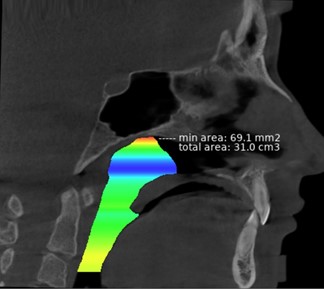

3D-цветная визуализация верхних дыхательных путей по 30 КЛКТ была выполнена с помощью программы Diagnocat. Искусственный интеллект определял общий объём верхних дыхательных путей от верхней границы (максиллярная плоскость ANS–PNS) до нижней границы (надгортанник), а также минимальную площадь поперечного сечения (MCSA). Наиболее частыми локализациями MCSA были:

У одного пациента из контрольной группы (CG), не имевшего аденоидов, искусственный интеллект определил объём верхних дыхательных путей до самой верхней границы носоглотки (основание черепа). MCSA в этом случае была зафиксирована под основанием клиновидной кости (рисунок 3).

У другого пациента из аденоидной группы (AG) была выраженная гипертрофия аденоидов (A/N = 0,83). Было отмечено, что у пациента со 2-й степенью гипертрофии аденоидов искусственный интеллект не выявил сужения или наличие патологии в области носоглотки. Чаще всего цветовая визуализация носоглотки отображалась синим или зелёным цветом, что соответствует объёму 300–360 см³, даже у пациентов с выраженной гипертрофией аденоидов.

Рисунок 3. Вид трехмерной цветной визуализации глоточных дыхательных путей с помощью Diagnocat.